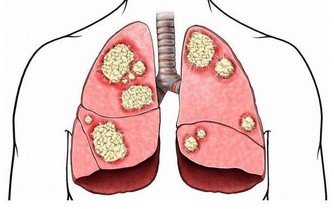

肝臟是人體中排毒解毒的重要器官,也是人體中最大的消化器官,生活中許多肝病患者是由於過度飲酒導致的,過度飲酒會增加肝臟以及腸胃的負擔,肝臟在人體內非常脆弱,起初患肝病,人體並沒有明顯症狀,因此,很多人錯過了治療肝臟最佳時期,當肝臟疼痛的時候,往往代表肝臟已經受損嚴重,生活中我們應該及時發現身體不適,定期去醫院做檢查,及時發現,及早治療。

一、身體出現這些現象,說明肝臟不健康,要及時發現,提前預防

肝臟不好的人,還會出現這些表現

1、皮膚出油,皮膚乾燥,頭髮容易出油

2、背部長大量粉刺,且背部容易出油

3、面色發黃,體形消瘦,牙齦出血

4、尿液發黃,尿液起沫,鞏膜發黃

5、眼睛乾澀,早晨起床眼屎多

6、食慾不振,腸胃消化不良,經常便秘

7、面色發黑,身體出現蜘蛛痣,肝掌